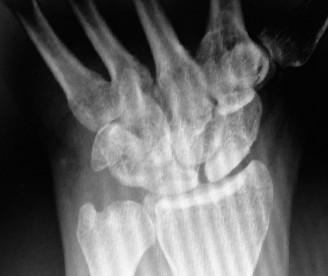

-

ray (Fig. 3–11) taken at the time of the visit is as shown. The radiologist reports this as SLAC wrist. What does SLAC stand for?

Figure 3–11(©) Sunil Thirkannad and Christine M. Kleinert.

The correct answer is (C).

The correct answer is (B). The patient has a severe SLAC wrist with involvement of the midcarpal joint. Loss of cartilage over the proximal pole of the capitate precludes a proximal row carpectomy. By the same token, interposition arthroplasty at the radio carpal joint alone fails to address the midcarpal problem. The use of a silastic prosthesis for the scaphoid has been abandoned due to very high rates of failure. Objectives: Did you learn...? Properly perform the Watson’s test? Identify a SLAC wrist and treat it? CASE 13 ### A patient presents with a history of chronic wrist pain of 6 years duration. He stated that he sustained a fall 9 years ago. Immediately after injury, he did not seek any medical attention, thinking that he had merely sprained his wrist. An xray taken at this visit is shown (Fig. 3–12). What does he have?